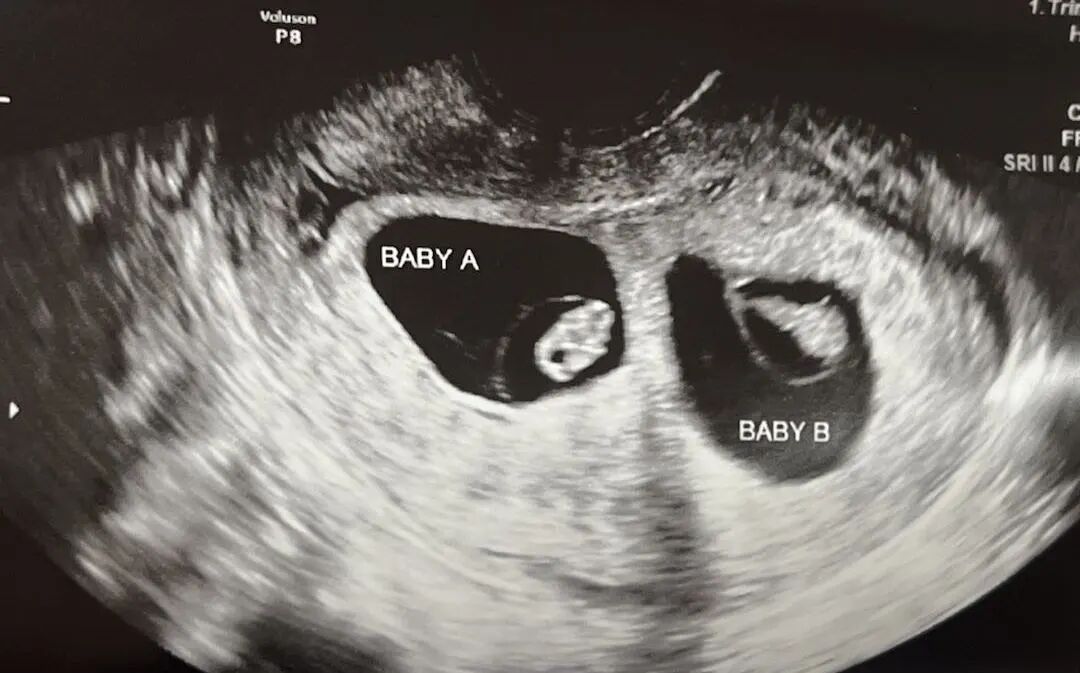

移植多个胚胎会有更高的受孕几率,但也会稍带更高的孕期风险。我们最近已经欢迎了许多双胞胎宝宝,已经开始充满期待,希望不久后能收到爱妈的好消息!